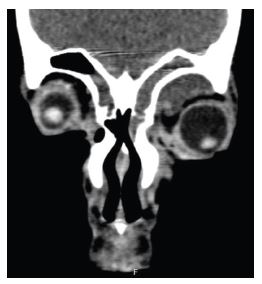

A previously healthy 16-year-old male presented to the Emergency Department with a 10-day history of edema and pain in the left upper eyelid and complaints of pain in the left thigh. He had no fever. On examination, erythema and edema with fluctuation of the left upper eyelid and frontal region were observed associated with proptosis and blurred vision. Additionally, he had edema, redness, heat and pain, and claudication in the left thigh and gluteal region. There were no signs of trauma, insect bites, or foreign bodies. The boy denied illicit drug use, namely intravenous use. Blood tests revealed leukocytosis (33,700 cells/μL) with neutrophilia (30,600 cells/μL) and elevated C-reactive protein (303 mg/L). Creatine kinase was normal. Computed tomography (CT) scan showed a multiloculated collection in the muscle planes of the thigh (Figure 1) and a partial thrombus in the left femoral vein. It also showed an expanding intraorbital lesion with proptosis and optic nerve extension (Figure 2). Empiric antibiotic therapy with ceftriaxone, clindamycin, and vancomycin was initiated, and the patient underwent surgical drainage of the intraorbital abscess and deep loculated collection in the left thigh. Methicillin-susceptible Staphylococcus aureus was isolated from blood and exudate cultures. During hospitalization, the boy remained persistently febrile despite analytical improvement. Thoracic, abdominal, and pelvic high-resolution CT scans were performed on day 8, showing bilateral cavitary lung lesions (Figure 3).

Figure 1 CT scan of the left lower limb on admission showing a multiloculated collection in the muscle planes of the left thigh.